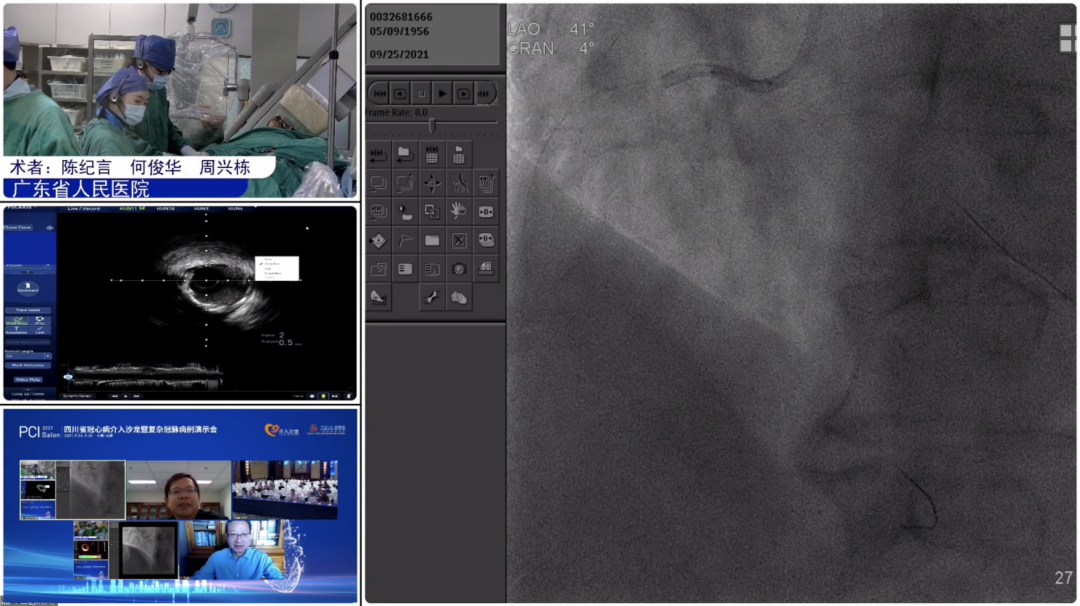

9月25日,大会隆重开幕,大会执行主席、四川大学华西医院贺勇教授主持,大会创始人及名誉主席、四川大学华西医院心内科黄德嘉教授,北京力生心血管健康基金会管廷瑞理事长,大会主席、四川大学华西医院陈茂教授,大会创始人及名誉主席东莞康华医院贾国良教授等多位专家领导分别以线上、线下参会形式共同出席开幕式,并为大会开幕致辞。随后,来自全国多地的冠脉领域资深术者通力配合,带来了11场极具难度和技巧的复杂冠脉病例手术演示及微课讲座。同期进行的护理及技术人员论坛、冠脉腔内影像与生理学论坛、冠心病诊疗论坛、降脂治疗论坛&心衰药物进展论坛、血栓抽吸、药物球囊、愈合型支架等专题学术内容应接不暇、精彩纷呈。